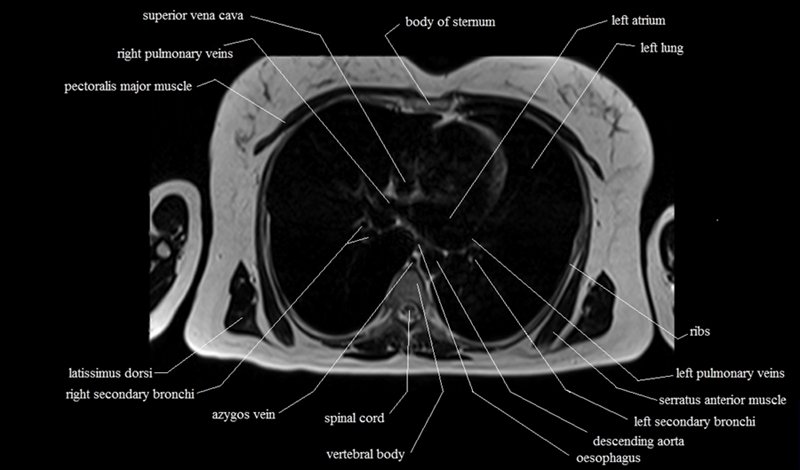

MRI Axial Cross Sectional Anatomy of Chest

This MRI chest (thorax) axial cross sectional anatomy tool is absolutely free to use. Use the mouse scroll wheel to move the images up and down, or alternatively, use the tiny arrows (→) on both sides of the image to navigate through the images. For a more detailed view, double-click the image to view it in full screen, and use the menu in the top right-hand corner to view individual slides or play them in a loop.